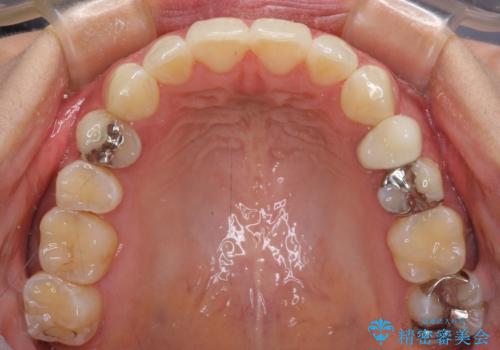

八重歯の再矯正 インビザラインでストレスなく矯正治療

- 学生の頃に矯正治療を行ったものの、保定を怠けてしまったことによる後戻りを気にして来院された患者様です。

根管治療が必要な歯があったため、矯正治療前に根管治療を行い、その後はインビザラインにより矯正治療を行うこととしました。

矯正治療後には根管治療を行った歯の補綴治療を行うこととしました。

下顎の八重歯が上顎歯列に収まる過程で咬みにくさがありましたが、最終的には、咬み合わせも安定し、きれいに歯列を整えることができました。